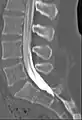

![]() Myelogram showing arachnoiditis in the lumbar spine. | |

Myelography is a type of radiographic examination that uses a contrast medium to detect pathology of the spinal cord, including the location of a spinal cord injury, cysts, and tumors. Historically the procedure involved the injection of a radiocontrast agent into the cervical or lumbar spine, followed by several X-ray projections. Today, myelography has largely been replaced by the use of MRI scans, although the technique is still sometimes used under certain circumstances – though now usually in conjunction with CT rather than X-ray projections.